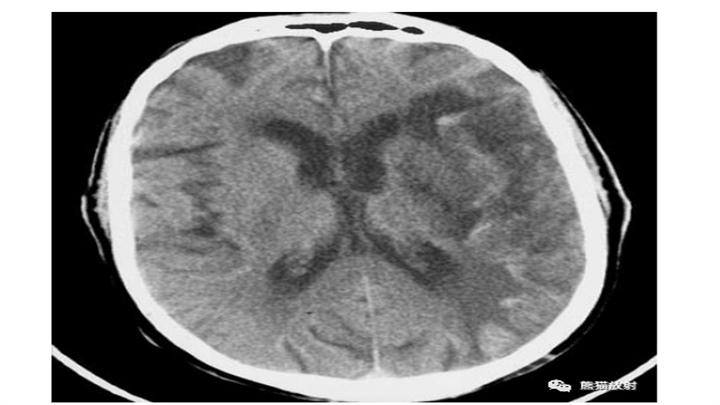

IPH随时间的演变。CT通常用于IPH随访中。上图为脑血肿患者在中风后数小时内的CT,注意病灶位置深,锯齿状边缘和小卫星灶的存在;中间图为14天后的CT,血肿体积缩小,密度减低,而周围水肿加重。下图为三个月后CT,病变被不规则低密度腔所取代,负占位效应,同侧侧脑室轻微扩张。